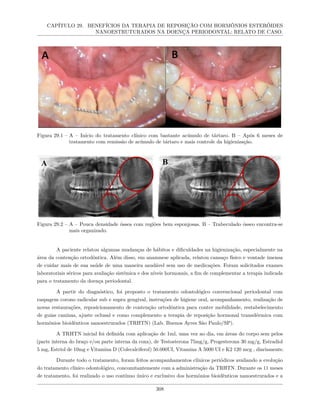

29 BENEFÍCIOS DA TERAPIA DE REPOSIÇÃO COM HORMÔNIOS ESTERÓIDES

NANOESTRUTURADOS NA DOENÇA PERIODONTAL: RELATO DE CASO. . . . . 305

29.1 Introdução . . . . . . . . . . . . . . . . . . . . . . . . . . . . . . . . . . . . . . . . . . . . . 306

29.2 Relato de caso . . . . . . . . . . . . . . . . . . . . . . . . . . . . . . . . . . . . . . . . . . 307

29.3 Análise e discussão . . . . . . . . . . . . . . . . . . . . . . . . . . . . . . . . . . . . . . . . 310

29.4 Conclusões . . . . . . . . . . . . . . . . . . . . . . . . . . . . . . . . . . . . . . . . . . . . 312